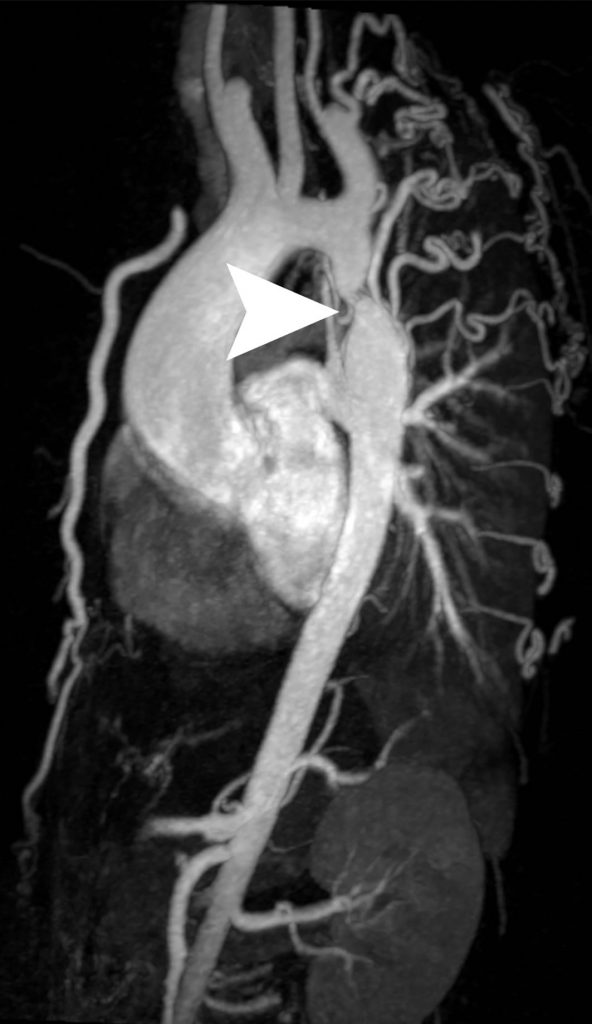

L’angio-IRM — plutôt que l’angioscanner pour éviter l’exposition aux rayons X chez l’enfant jeune, conformément à la directive Euratom 97/43 — permet de mettre en évidence la sténose aortique et de faire le bilan complet de l’affection en préthérapeutique : recherche d’hypoplasie de l’arc aortique, quantification et longueur de la sténose et topographie exacte, étude de la valve aortique et de la fonction cardiaque (figure 36.1).

Fig. 36.1. Angio-IRM de l’ensemble de l’aorte en reconstruction 3D et vue sagittale oblique.

Coarctation de l’aorte : sténose aortique courte en regard de l’isthme (tête de flèche), avec dilatation post-sténotique et de nombreuses artères collatérales hypertrophiées (notamment les artères intercostales).

Source : CERF, CNEBMN, 2022.

III. Sémiologie

La coarctation aortique se présente le plus souvent sous la forme d’une sténose courte de l’aorte thoracique, siégeant en regard de l’isthme, avec parfois une dilatation post-sténotique de l’aorte sous-jacente et une dilatation des artères intercostales.